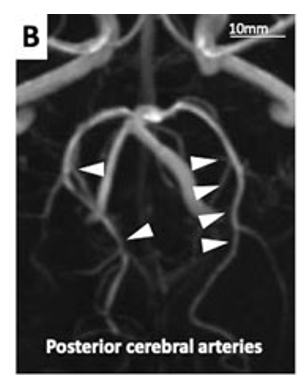

Tacrolimus, a drug suspected to cause the RCVS, was discontin- ued although its blood concentration was within the target range, and cyclosporine was given instead. The symptoms immediately improved and never recurred. Signs of allograft rejection were not observed and she was discharged without any neurological complications. Release of cerebrovascular constrictions was observed on subsequent brain magnetic resonance angiography (MRA) three months after discharge (Figure 2B, white arrow- heads).

Figure 2B: Magnetic resonance angiography done three months after discharge. Vasoconstriction of cerebral arteries improved (white arrowheads).